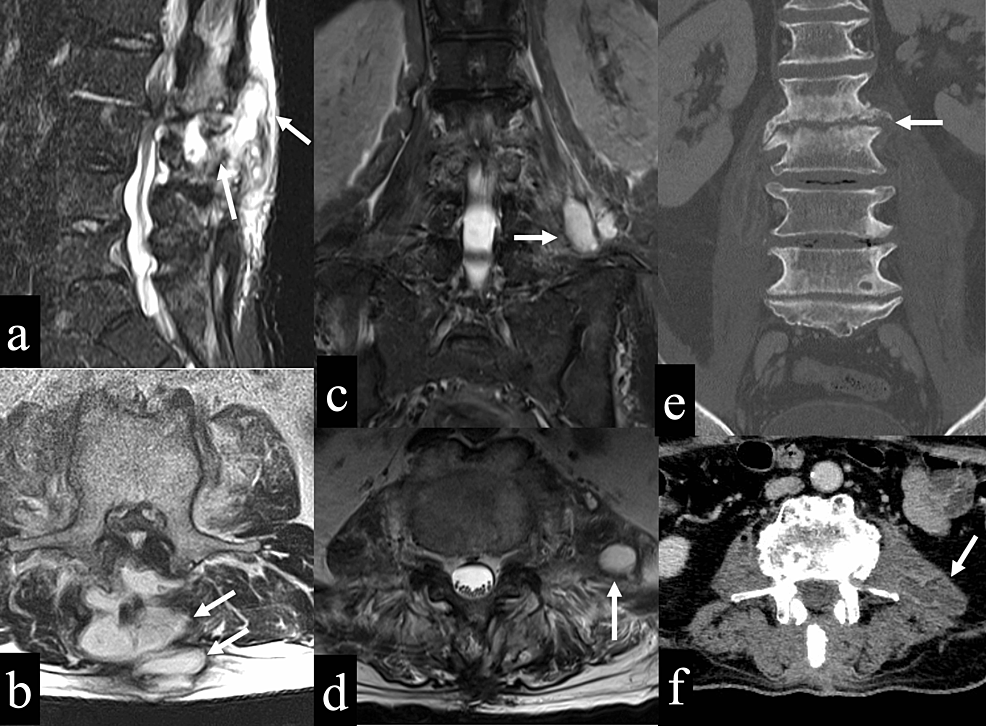

From associationofanaesthetists-publications.onlinelibrary.wiley.com

Spinal haematoma after removal of a thoracic epidural catheter in a Vitamin K Deficiency Coagulopathy specific deficiencies in coagulation factors, such as fibrinogen, may be corrected by administration of purified coagulation factor. vitamin k has a major role in coagulation pathways because it is a cofactor required for the activity of several key. addressing vitamin k deficiency in icu patients is crucial for mitigating risks associated with critical illness, yet optimal. Vitamin K Deficiency Coagulopathy.